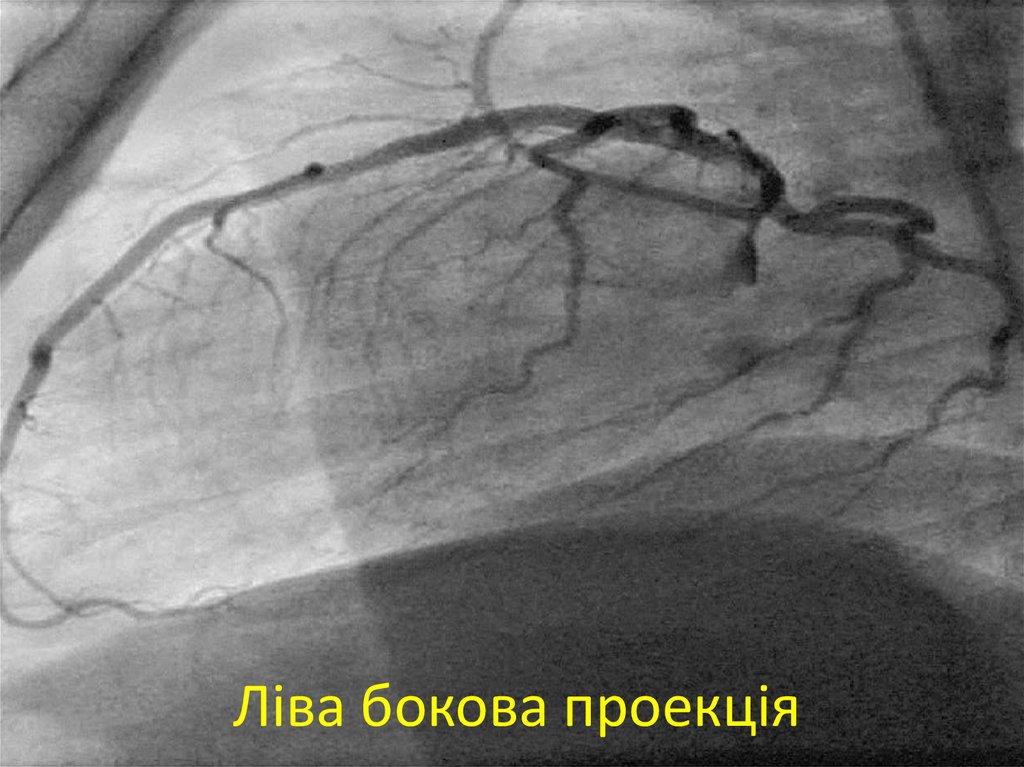

27. Ліва бокова проекція

28. Ліва бокова проекція

29. Ліва бокова проекція